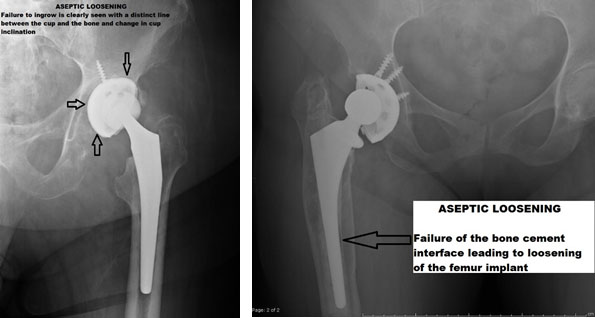

ASEPTIC LOOSENING

It is an inflammatory process where there is a loosening of the implant-bone interface leading to symptoms and reduction in quality of life. It usually is a long-term phenomenon and progresses gradually.

Radiology-

X rays usually demonstrate a clear line between the un-cemented cup, femoral stem, and bone, as shown in the following examples. Aseptic loosening can also be seen in cemented THR, where there will be a clear line demarcating cement bone interface.

ASEPTIC LOOSENING IN CEMENTED THR

The principle in cemented loosening is slightly different.Here, the particles generated by friction between the head of the femur and the acetabular component penetrates the area between the cemented shell and bone, leading to progressive loosening of the interface.